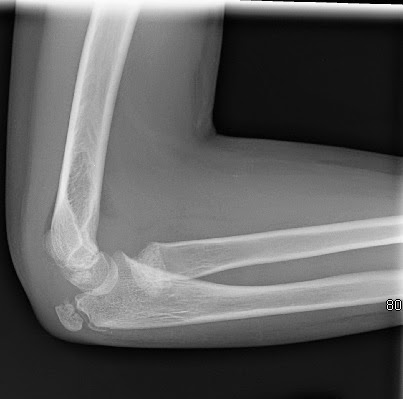

Локтевой перелом форум

Локтевой перелом форум 115 фото